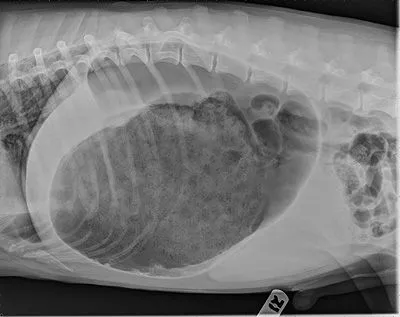

GDV or "BLOAT"

• Radiography